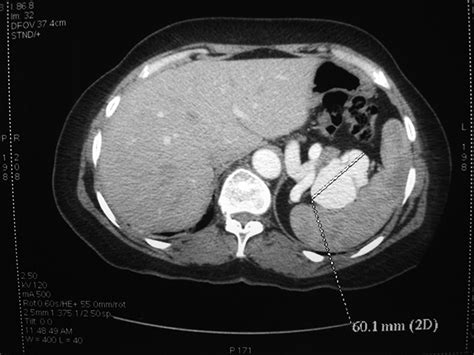

Computed Tomography (CT) Scan: Provides detailed cross-sectional images of the abdomen. It is often used to confirm the presence of an aneurysm and assess its size and location.